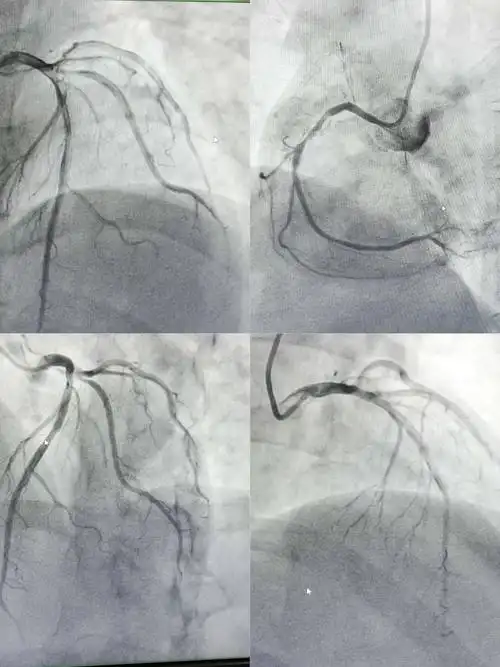

清晰的心脏冠脉造影图片!